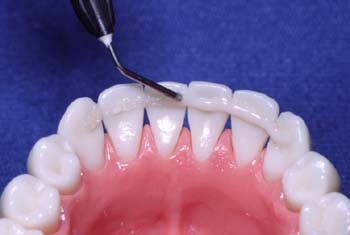

Humedezca la fibra Ribbond con un adhesivo sin relleno (sellador). Adapte la fibra en el composite. Al igual que con los brackets, el retenedor fijo de Ribbond debe estar unido al diente lo más estrechamente posible.

Sujete con el dedo la fibra ya adaptada. Utilice un instrumento para colocar la fibra en los contactos interproximales lo más cerca posible de la superficie del diente. Continúe diente tras diente hasta colocar todo el retenedor.

La colocación de un retenedor Ribbond es diferente al de un alambre. Ribbond se adapta lo más cerca posible y muy profundamente en los contactos interproximales.

Después de la colocación, quite la resina sobrante y polimerice.

Usando pinceles aplicadores, instrumentos o jeringas con punta de aguja, aplique una capa delgada de resina fluida sobre la fibra. Polimerice.